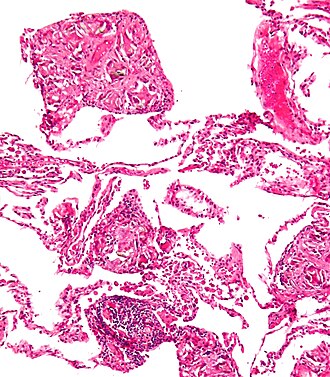

Micrograph showing pulmonary talcosis. H&E stain.